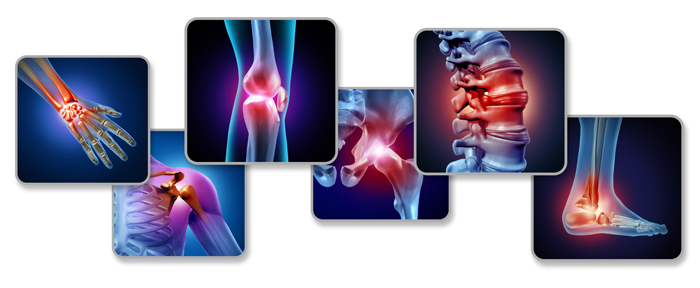

পিঠের মেরুদন্ডে ব্যথা এমন একটি সমস্যা যা প্রায় সকল বয়সের মানুষের মধ্যেই দেখা যায়। এই সমস্যা কখনও কখনও এতটাই তীব্র হতে পারে যে এটি দৈনন্দিন কাজকর্মে ব্যাঘাত ঘটাতে পারে। পিঠের মেরুদন্ডে ব্যথার বিভিন্ন কারণ থাকতে পারে, যা সঠিকভাবে নির্ণয় ও চিকিৎসা করা গুরুত্বপূর্ণ। আমরা পিঠের মেরুদন্ডে ব্যথার কারণগুলি বিশ্লেষণ করব এবং এই সমস্যা থেকে মুক্তির উপায় নিয়ে আলোচনা করব।

মেরুদন্ডের ডিস্কের সমস্যা যেমন হার্নিয়েটেড ডিস্ক বা স্লিপড ডিস্ক পিঠের মেরুদন্ডে ব্যথার একটি সাধারণ কারণ। এই সমস্যায় মেরুদন্ডের ডিস্ক সরে গিয়ে নার্ভে চাপ সৃষ্টি করে, যা তীব্র ব্যথার কারণ হতে পারে।

আর্থ্রাইটিস মেরুদন্ডে ব্যথার একটি সাধারণ কারণ। বিশেষ করে বৃদ্ধ বয়সে এই সমস্যা দেখা যায়, যেখানে সন্ধিগুলি ফোলাভাব, ব্যথা এবং শক্ত হয়ে যায়।

অস্টিওপরোসিস একটি হাড়ের সমস্যা, যেখানে হাড়ের ঘনত্ব কমে যায় এবং হাড় দুর্বল হয়ে যায়। এর ফলে মেরুদন্ডে ফ্র্যাকচার হতে পারে এবং পিঠের মেরুদন্ডে ব্যথা দেখা দিতে পারে।